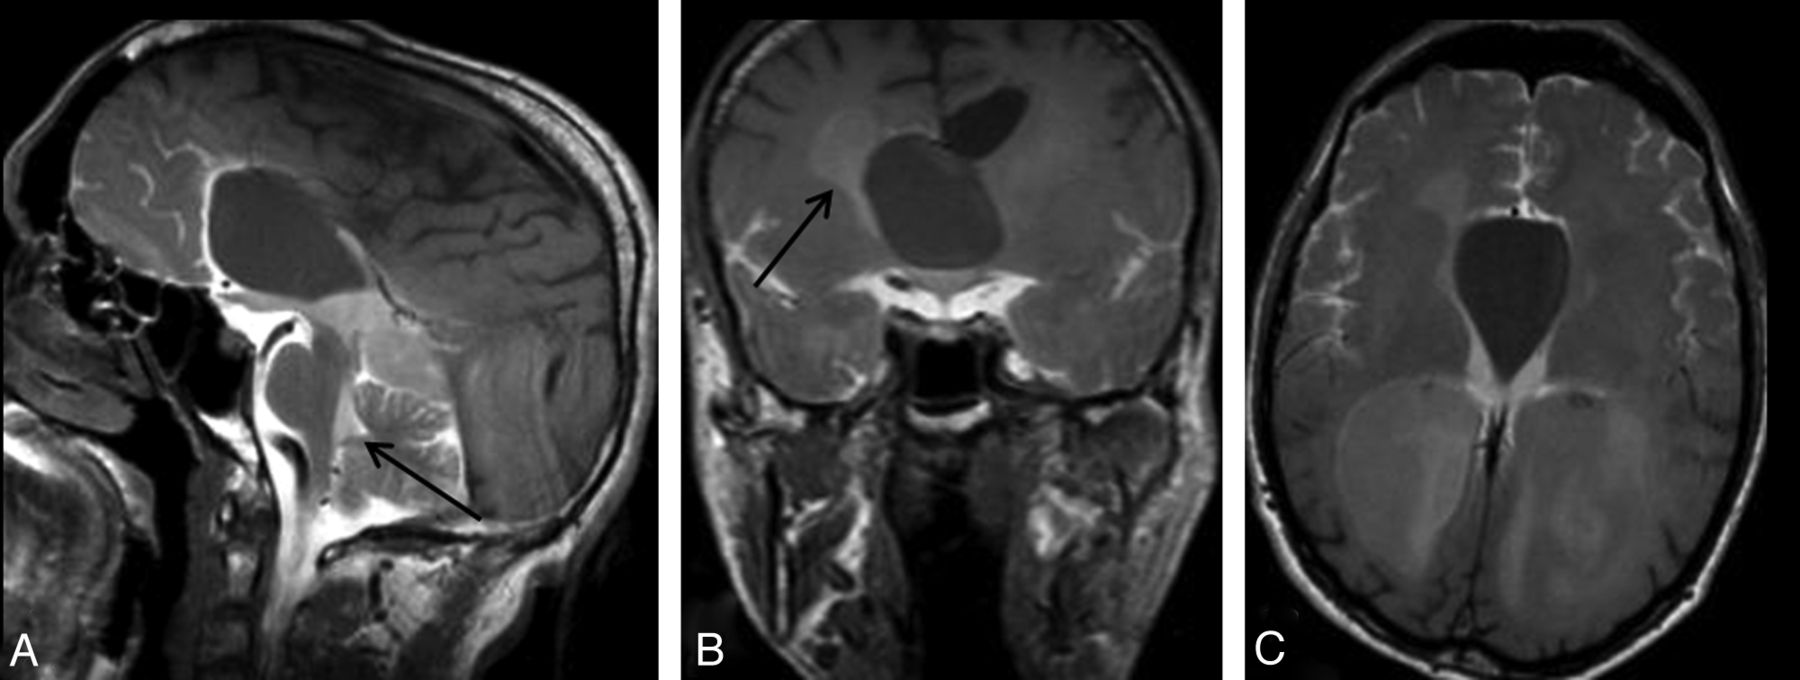

Routine MR imaging sequences are usually limited in depicting the etiology of hydrocephalus and demonstrating the presence of AS (Fig 5).37 The basic criteria for diagnosis of AS in routine sequences are triventricular dilatation with a comparatively small fourth ventricle, narrowing of the aqueduct, and expansion of third ventricle borders and recess.9,38 However, most of these criteria are subjective; therefore, more effective techniques are needed.39 Additionally, MR imaging plays a critical role in treatment planning of patients with AS, specifically for selection of the appropriate surgical procedure (such as ventriculoperitoneal shunt, ETV, or endoscopic aqueductoplasty).9,37,40

A 20-year-old man with headache. Sagittal 3D-CISS (A) and precontrast T1WI (B) shows hydrocephalus. Sagittal 3D-CISS image demonstrates a linear hypointense band at the cerebral aqueduct (arrow in A). The inferior wall of the third ventricle cannot be depicted clearly on 3D-CISS image (A). Early-phase postcontrast sagittal and coronal T1WI shows passage of the intrathecally administered contrast to the fourth ventricle, but not to the third ventricle (arrows) (C, D). Imaging findings are consistent with aqueductal stenosis and hydrocephalus secondary to a web. A 12-hour post injection axial sequential T1WI showed no relation between the basal cisterns and the third ventricle (E-G). The intact third ventricular floor implies absence of a STV, and tells us ETV or shunt procedures are necessary.